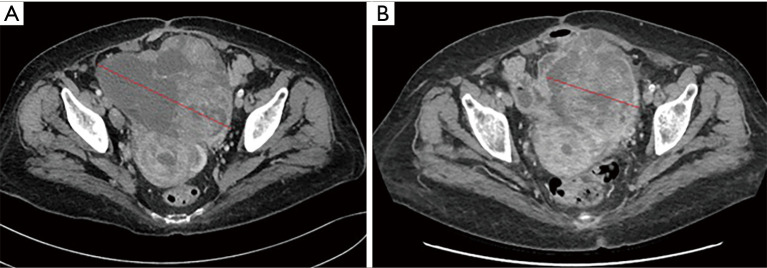

Case description: A 75-year-old woman with EC (MSI-H) with pulmonary and bone metastasis progressed on first line chemotherapy platinum-containing, was treated with dostarlimab as monotherapy. Medical history was positive for arterial hypertension, autoimmune thrombocytopenia and allergy to amoxicillin and levofloxacin. After the second administration of dostarlimab, our patient showed a dramatic improvement of her clinical conditions. The clinical response was confirmed by radiological response on the basis of the results of a computed tomography (CT) scan performed in March 2023 that showed a reduction of the pelvic mass and pulmonary secondaries. No toxicities related to autoimmune thrombocytopenia occurred. The experienced grade 2 infusion reaction, resolved with the suspension of the drug and the administration of an antihistaminic drug; then we resumed dostarlimab doubling the administration time.